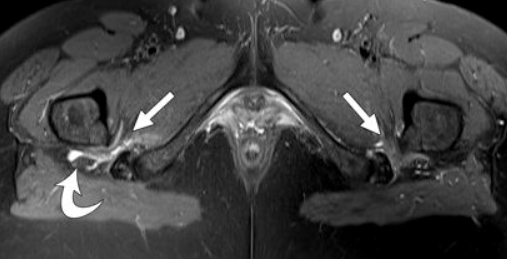

주로 증상과 이학적 검사로 진단하며, 필요시 MRI, 초음파, CT 등을 통해 다른 원인 감별 및 이상근의 상태, 좌골신경 압박 여부를 확인합니다.

허리디스크 등과 구별이 중요하기 때문에 정확한 진단이 필요합니다.